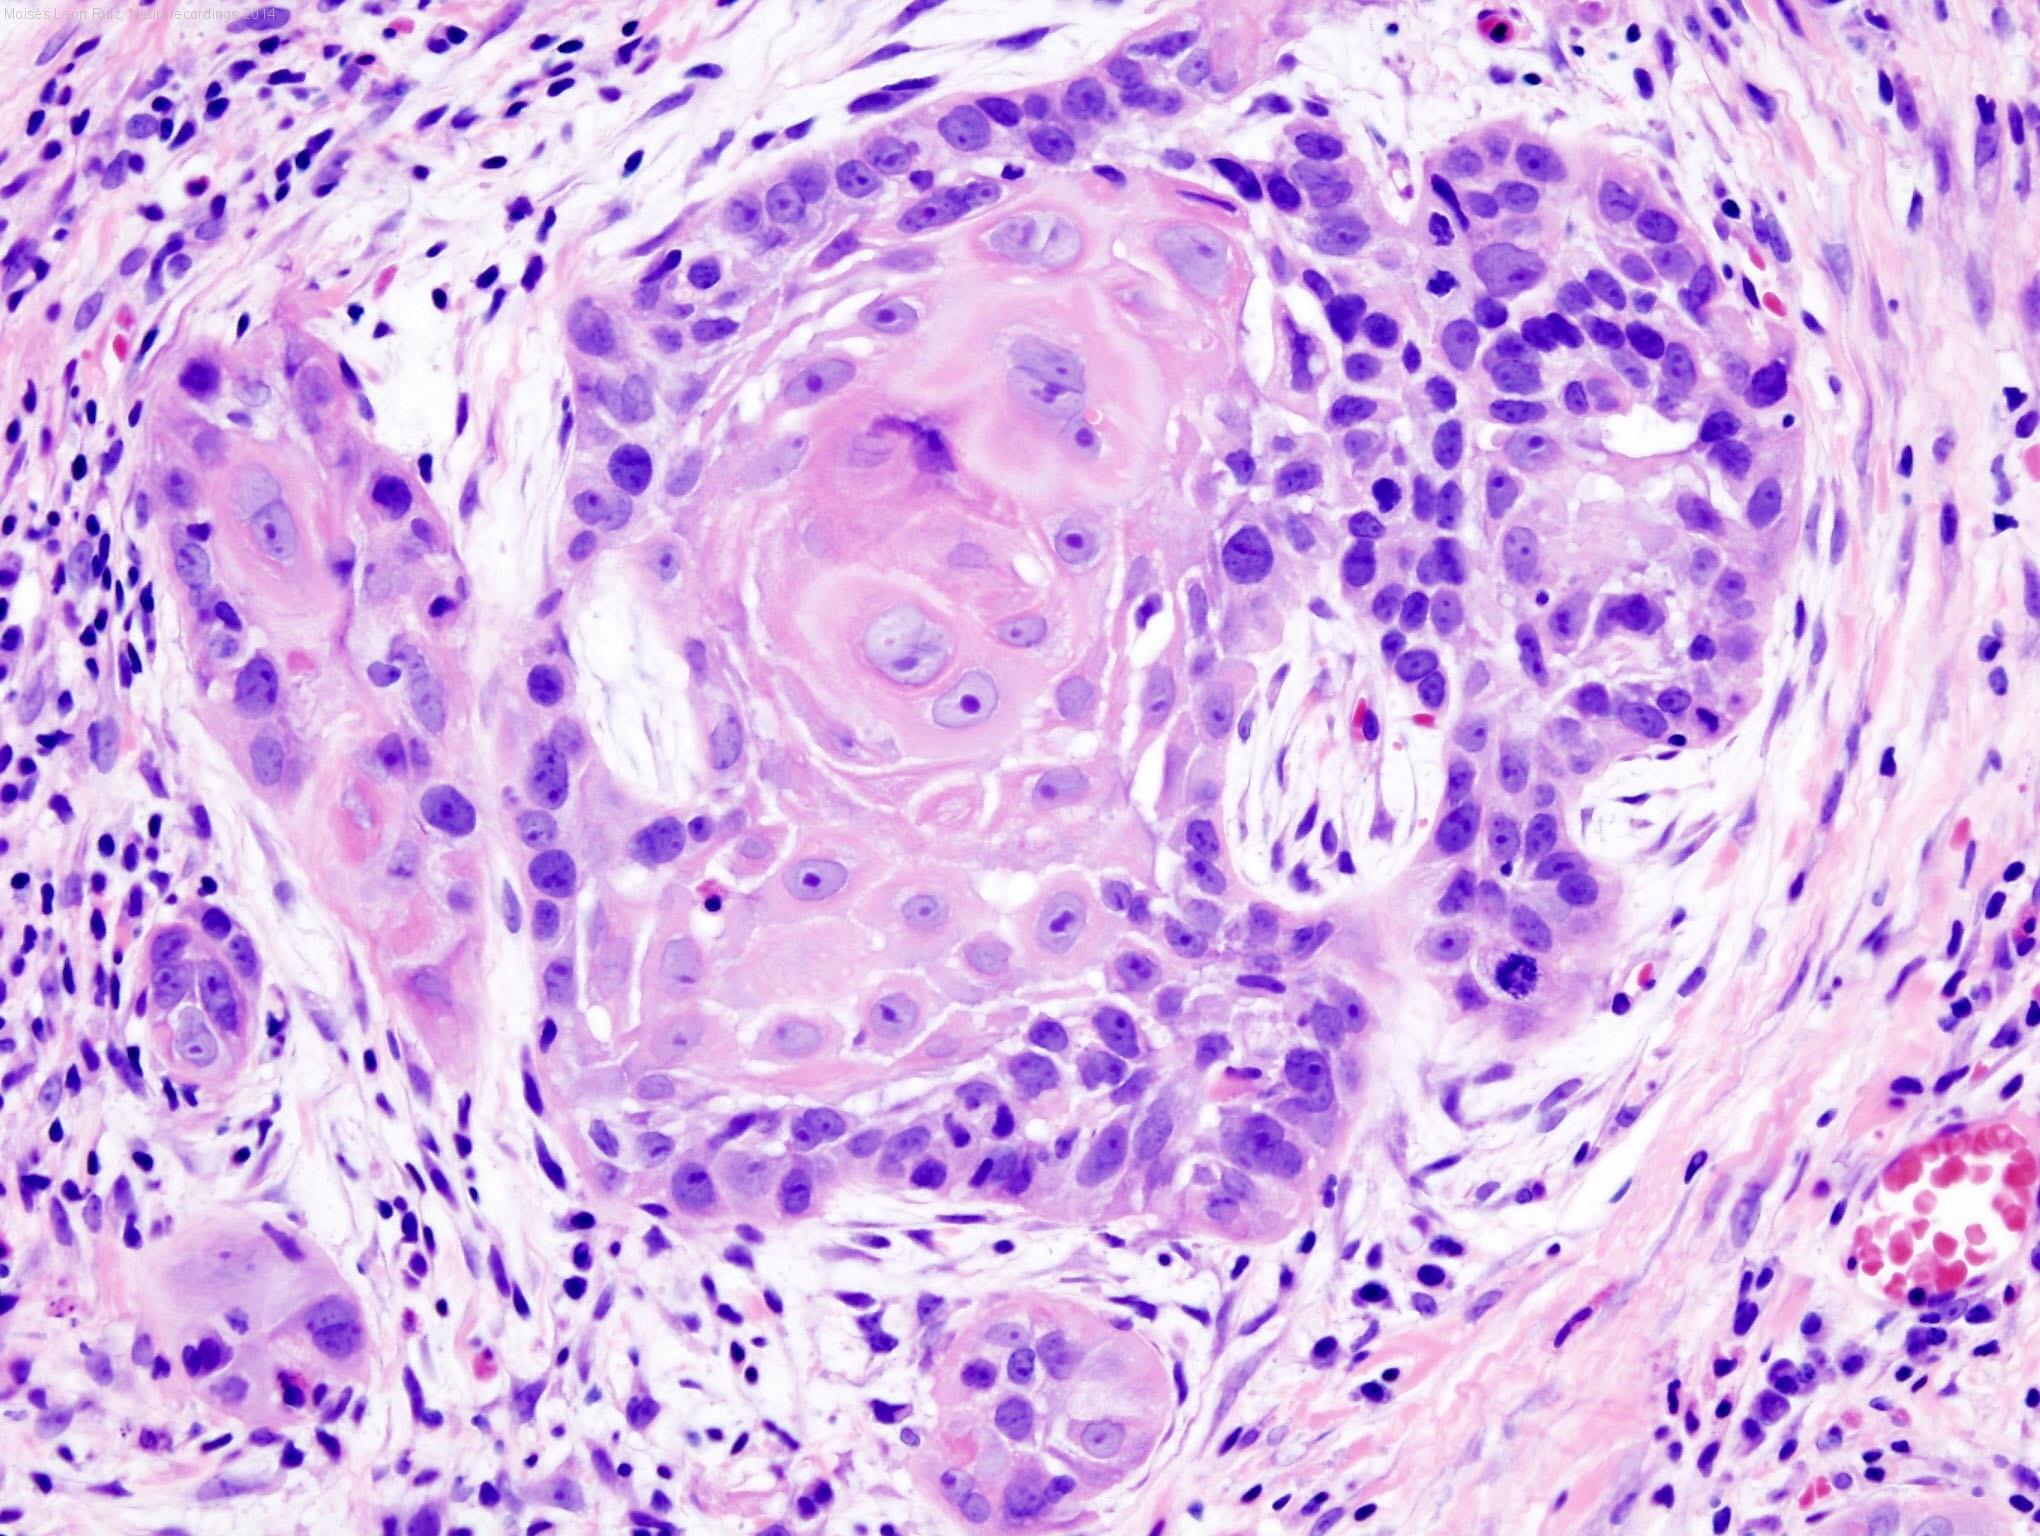

Diagnóstico final: PRIMER CASO DESCRITO DE ESTADO DE MAL EPILÉPTICO SECUNDARIO A METASTATIZACIÓN CRÁNEO-CEREBRAL COMO FORMA DE DEBUT DE UN CARCINOMA EPIDERMOIDE LARÍNGEO SUPRAGLÓTICO